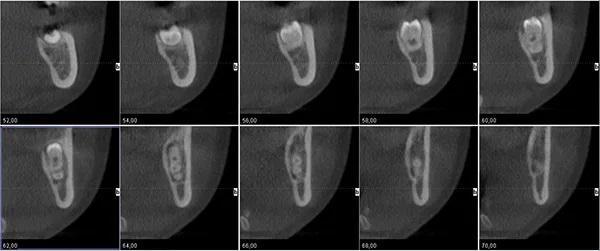

Чтобы определить соотношение рисков и преимуществ и план лечения, ситуация потребовала изучения взаимного расположения между корнями третьего моляра и нижним альвеолярным нервом (НАН). Для точного определения положения НАН относительно деформированного третьего моляра была использована конусно-лучевая компьютерная томография (КЛКТ). НАН проходил в язычном направлении до корней моляров (Фото 2). Кроме того, КЛКТ была использована для расчета общей мезиодистальной длины коронки, которая, как было определено, составила 15,56 мм.

Фото 2: КЛКТ, показывающая связь между “двойным зубом” и положением НАН.